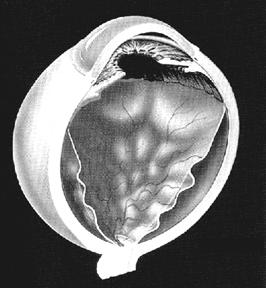

Decolarea de retina reprezinta separarea celor doua straturi embrionare ale retinei (epiteliul pigmentar si neuroepiteliul) intre care nu exista jonctiuni celulare. Acest spatiu virtual este un vestigiu al cavitatii centrale a veziculei optice; se vorbeste de decolare de retina atunci cand acest spatiu devine real, dar de fapt asa cum am aratat este vorba numai de decolarea neuroepiteliului, cu dedublarea retinei (Fig. 17.8)

Fig. 17.8 - Decolare de

retina - aspect schematic

Fig. 17.9 - Decolare de

retina - aspect oftalmoscopic

Examenul oftalmoscopic - se face prin oftalmoscopie directa

si indirecta. Retina decolata are aspect cenusiu si se onduleaza usor la

miscarile ochiului (caracterul mobil). Dupa decubit dorsal mai

multe ore retina se reaplica partial si decolarea este de mai

mici dimensiuni. La nivelul retinei decolate vasele fac cot si au traiect

ondulat. De asemenea la examenul oftalmoscopic este necesara

evidentierea rupturilor retiniene, deoarece tratamentul include

fotocoagularea acestor zone prin care se acumuleaza lichid in spatiul

de clivaj (Fig. 17.9 - vezi

plansa).